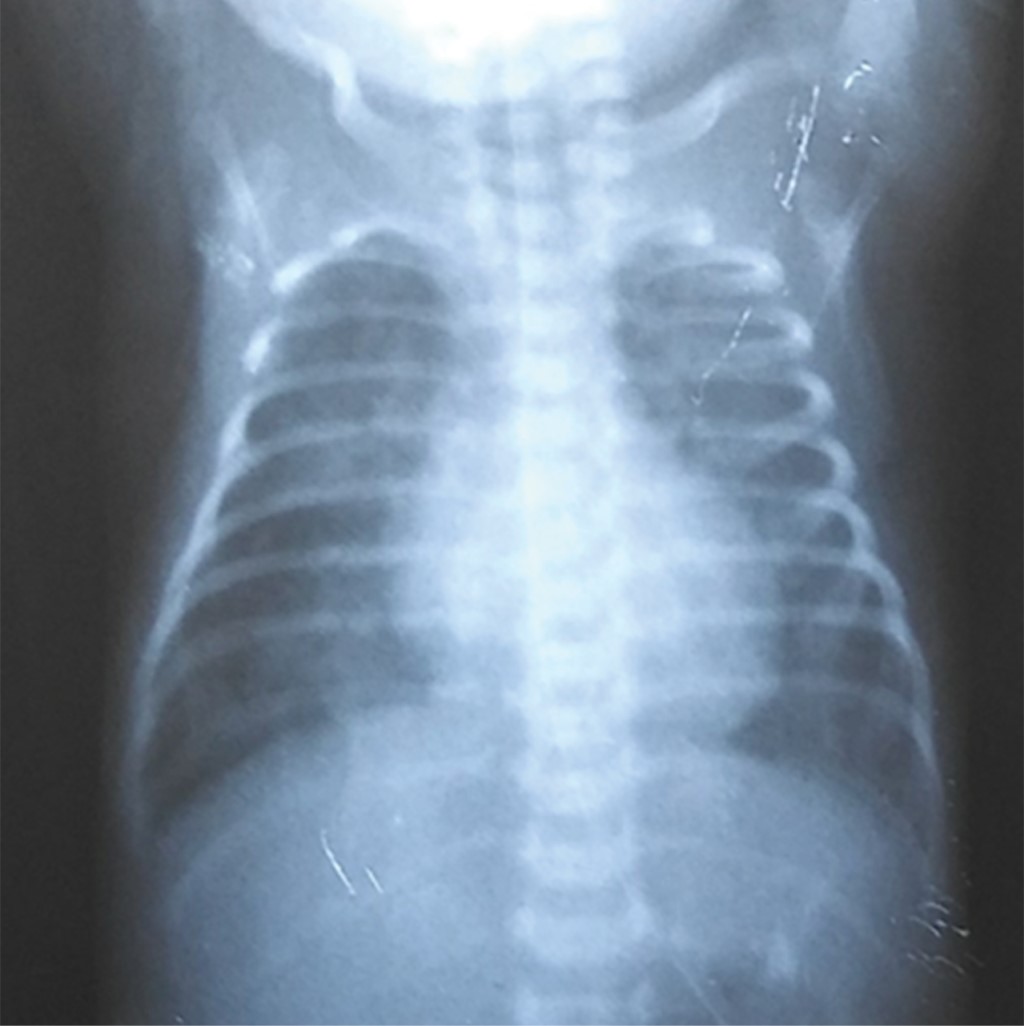

Unilateral interstitial pulmonary emphysema in a newborn

Objective: To describe the clinical outcome of a newborn (NB) with unilateral pulmonary interstitial emphysema (PID) who required selective ventilation of the contralateral lung. Case presentation: This is a 32-week gestation female newborn, who presented respiratory distress syndrome (RDS), requiring mechanical ventilation. On the second day of life, she presented left unilateral interstitial PID. High-frequency oscillatory ventilation was used as treatment for this complication, as well as positioning of the newborn on the affected side, but there was no improvement. Subsequently, after selective ventilation of the contralateral lung was used for 48 hours total resolution of the emphysema was achivied. Conclusion: PID is a serious complication in newborns. The use of selective ventilation to the contralateral lung is a therapeutic alternative for its resolution.

Figure 2